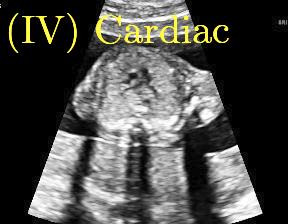

Row I in Fig. 6 shows a fetal brain image from . The confidence estimation of shadow regions from the baseline, the proposed method and the proposedAG method are similarly accurate since we use fetal brain images to train the confidence estimation networks in these three methods. These outperform [16] and [22]. Rows (II-IV) in Fig. 6 show shadow confidence maps of non-brain anatomy from , including lips, abdominal and cardiac. The baseline failed on unseen data during inference. However, the proposed methods are able to generate accurate shadow confidence maps because of the generalized shadow features obtained by the shadow-seg module. Furthermore, the “Lips” example shows that our method is capable of detecting weaker shadow regions that have not been annotated in manual segmentation. This indicates that the confidence estimation network has learned general properties of shadow regions.